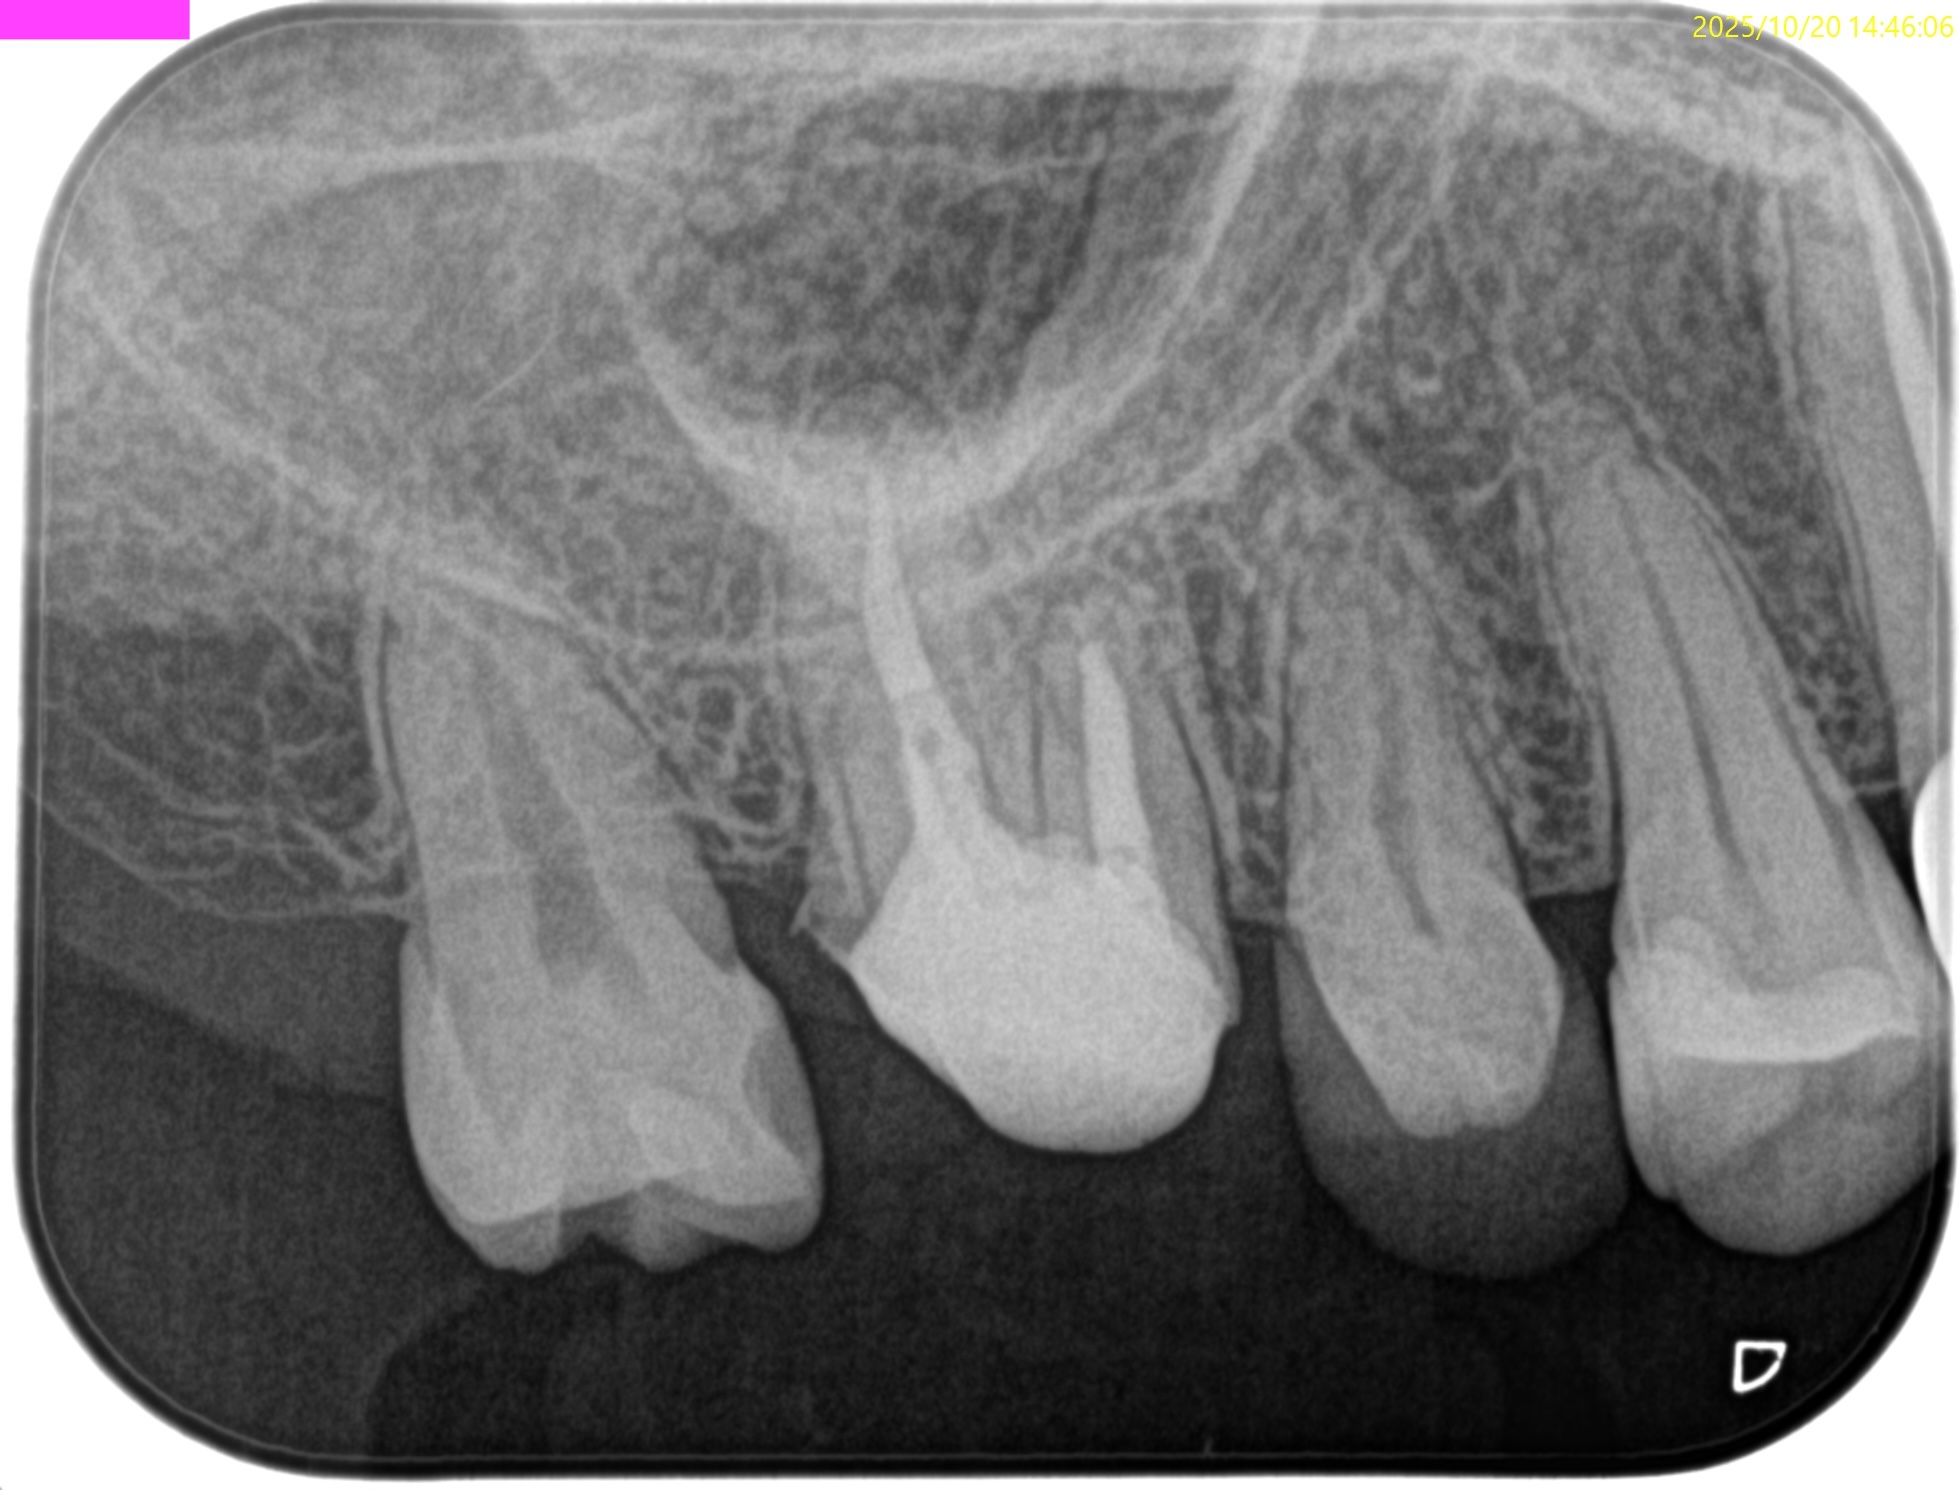

PA(2024.7.1)

#3

MB

DB

P

MB,DB,Pと3根全てに病変がある。

#14

MB,DBには病変がないが、Pに存在する。

#16

歯内療法学的診断(2024.7.1)

Pulp Dx: Previously treated

Periodical Dx: Symptomatic apical periodontitis

Recommended Tx: Re-RCT